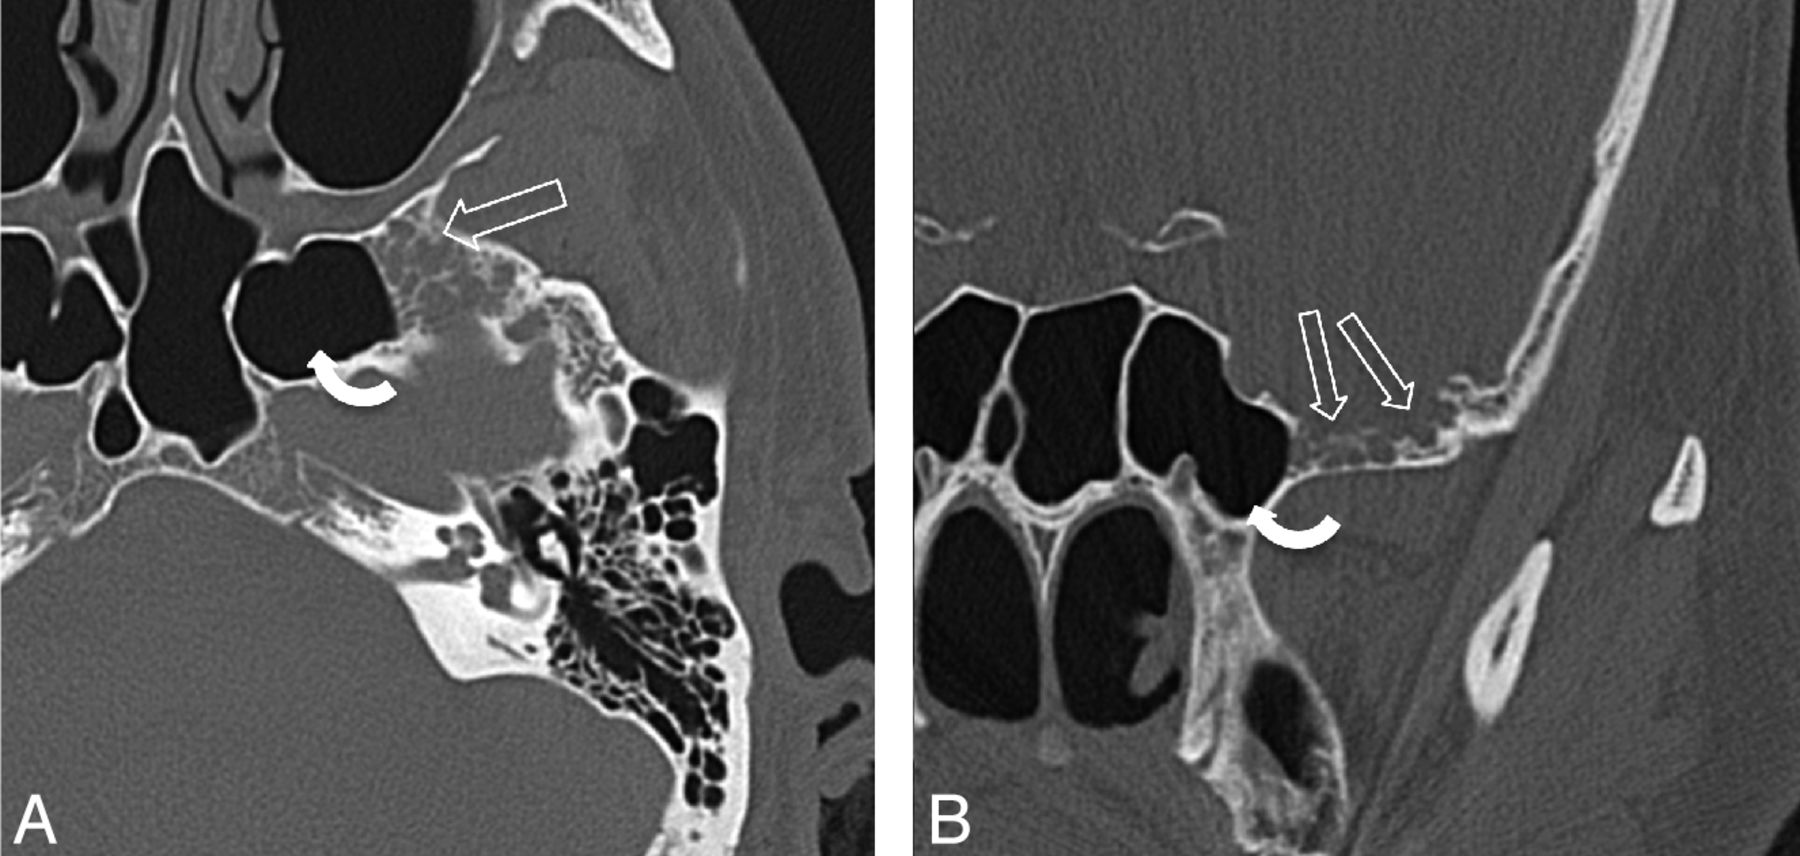

A 43-year-old man presenting with headaches (patient 20). A, Axial bone CT image through the mid SS shows multiple ovoid bony defects in the greater wing of the sphenoid bone representing arachnoid pits due to aberrant arachnoid granulations (open arrows). This patient also has extensive pneumatization of the lateral recesses of the SS (curved arrow). B, Coronal CT image of the same patient as in panel A, again demonstrating multiple arachnoid pits in the GWS (open arrows). A cephalocele was seen on MR imaging (not shown here).